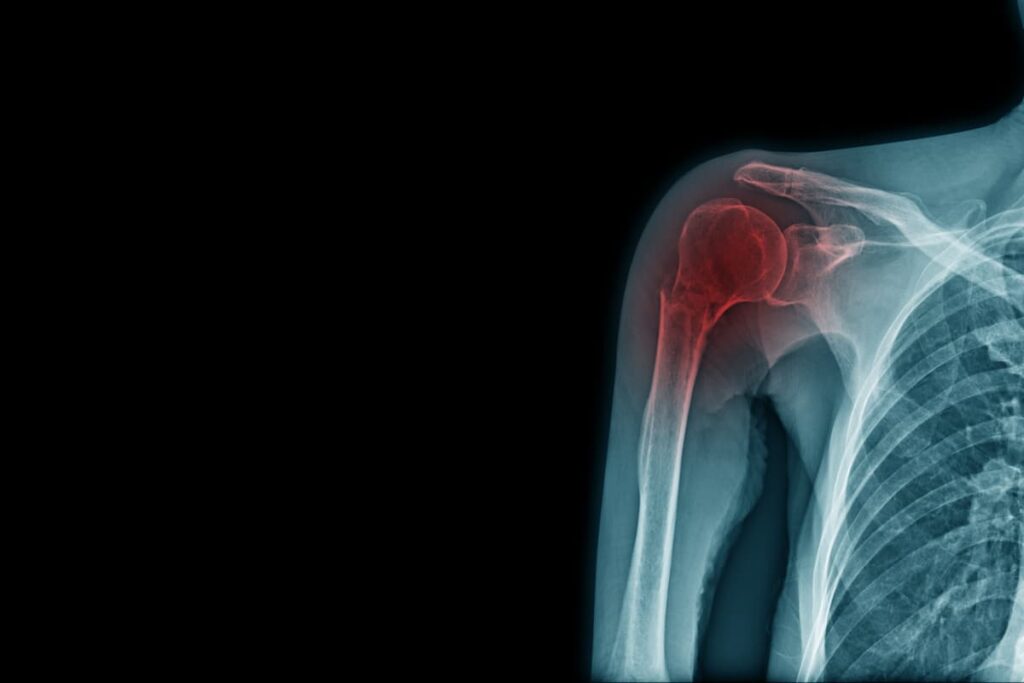

The rotator cuff is a group of muscles and tendons that keep the upper arm bone secure in the shoulder socket. These tissues can be easily damaged in accidents, including motor vehicle crashes, slips and falls, and workplace injuries. When injured, rotator cuff damage can cause pain and limit movement, making prompt treatment essential to avoid complications.

The rotator cuff is a group of four muscles and tendons that surround your shoulder joint. It plays a critical role in allowing you to lift and rotate your arm, making everyday activities like reaching overhead, lifting, and throwing possible. Because of its key function and frequent use, the rotator cuff is prone to injury.

- X-ray: While an X-ray doesn’t show soft tissues like tendons, it can help rule out bone fractures or joint problems. It can also reveal signs of wear and tear, such as bone spurs, which might be contributing to your symptoms.

- MRI (Magnetic Resonance Imaging): An MRI is the most effective way to visualize soft tissue injuries like rotator cuff tears. It provides detailed images of the tendons and muscles, helping doctors determine the extent of the injury, whether it’s a partial tear or a complete rupture, and whether surgery may be needed.